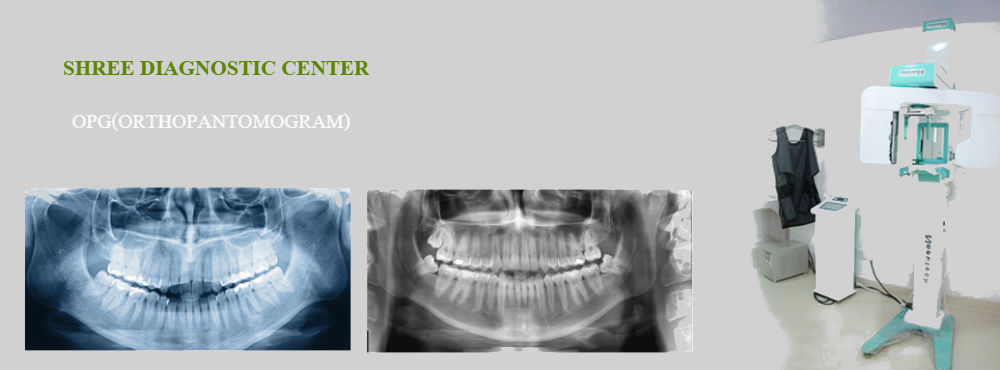

opg

An OPG is a panoramic or wide view x-ray of the lower face, which displays all the teeth of the upper and lower jaw on a single film. It demonstrates the number, position and growth of all the teeth including those that have not yet surfaced or erupted. It is different from the small close up x-rays dentists take of individual teeth. An OPG may also reveal problems with the jawbone and the joint which connects the jawbone to the head, called the Temporomandibular joint or TMJ. An OPG may be requested for the planning of orthodontic treatment, for assessment of wisdom teeth or for a general overview of the teeth and the bone which supports the teeth.